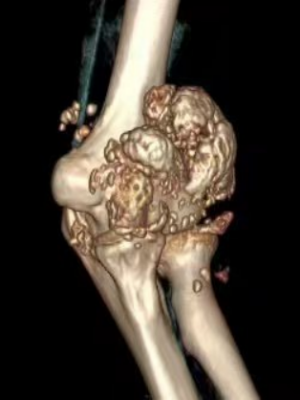

“经过完善核磁检查,发现患者的左肘关节内布满了密密麻麻、大小不一的颗粒,符合滑膜软骨瘤病的诊断,这种情况需要接受手术治疗。”据运动医疗、关节骨病科主任医师余敏介绍,明确诊断后,余敏医疗组为患者实施了肘关节镜下微创手术,取出了大量的滑膜软骨瘤病灶——千余颗外形看上去像“珍珠”的白色颗粒。手术仅仅需要通过数个几毫米大小的孔,就将肘关节内的滑膜软骨瘤清除干净,手术过程非常顺利,术后患者肘关节活动较术前明显恢复。

为什么这位年轻小伙肘关节内会长出这么多的“珍珠”呢?余敏介绍,滑膜软骨瘤病又称滑膜软骨化生,是一种不常见的良性关节病,是由滑膜软骨化生而引起的一种关节病。以滑膜上形成软骨结节为特征,这些软骨小体多呈砂粒状,可带蒂生长,向关节腔内突出,亦可脱落进入关节腔内,成为游离体(又称为关节鼠),受关节滑液滋养而逐渐长大,后期软骨结节可发生钙化或骨化,所以也称滑膜骨软骨瘤病。好发于膝、髋、肘、肩关节。可导致关节积液,肿胀,活动受限,往往出现关节突然锁住感,不能伸直和屈曲。稍活动后,常出现弹响,随后症状消失。